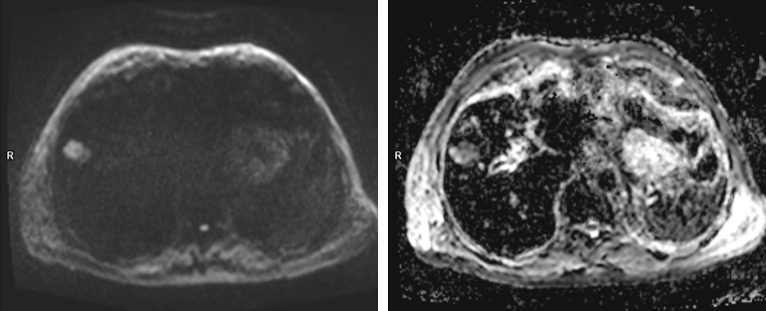

Figura 2: Axial difuzie

Pacientul era cunoscut cu polipoza adenomatoasă și i s-a descoperit întâmplător la ecografie o leziune expansivă hepatică. Pe examinarea CT nu a putut fi caracterizat convenabil iar la examinarea IRM s-a decelat o leziune spontan în hipersemnal T1 cu priză de contrast în timp precoce și fenomen de spălare rapidă a contrastului în timp venos / tardiv.